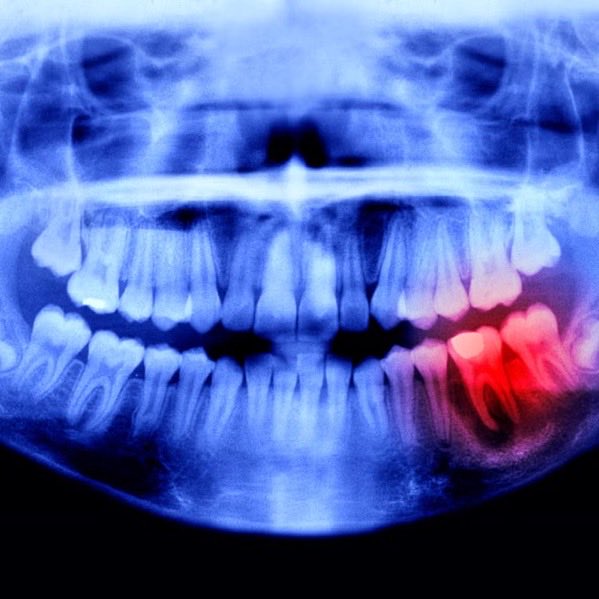

Diş tedavisinde tarihi buluş geliyor. Japon bilim insanları, implantı tarihe gömecek ilaç keşfinin arefesinde.

Japon bilim insanları, diş tedavileri ile ilgili harekete geçti ve kaybedilen dişlerin yeniden kazanılması için mükemmel bir yöntem geliştirdi.

Gelen bilgilere göre tüm testleri geçmesi durumunda ilacın çekilen, kaybedilen dişin yerine yeni diş çıkaracağı bildirildi.

Tüm testlerden geçmesi durumunda 2030 yılında söz konusu ilacın piyasaya sürüleceği öğrenildi